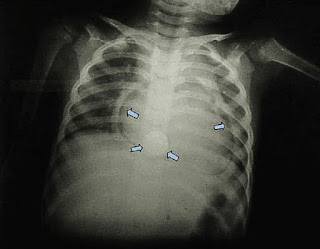

![]() |

| Presencia de dos BB en esófago de niño |